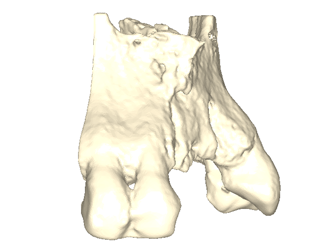

Yngre kvinne som mistet tenner 11-22 gjennom traume. Både en horisontal og vertikal defekt i et estetisk utfordrende område. En Yxoss 3D-printet membran produseres gjennom planleggingsverktøyet, i dette tilfellet IO-skanning og CBCT som grunnlag. En preprotetisk voksing på den tiltenkte suprakonstruksjonen produseres for å forutsi fremtidig protese og tiltenkt beinvolum. Partikulært bein påføres membranen som deretter fikseres på plass. Etter 6 måneders helbredelse fjernes membranen. Regenerert bein uten pseudoperiosteum er påvist, implantater kan plasseres med gode marginer og god protesetilstand.

Beindefekt som følge av traume

Planlegging av Yxoss membran